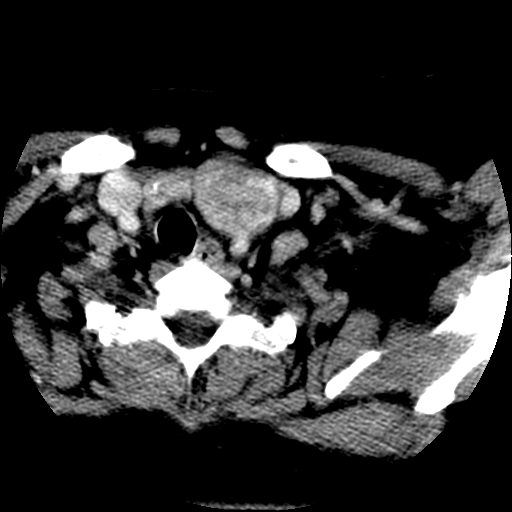

标题: CT25491:女,55岁,发现左侧甲状腺肿块一个月。 [打印本页]

女,55岁,发现左侧甲状腺肿块一个月,彩超示:甲状腺多发结节伴左叶结节液化。

左右叶都有,峡部也受累,有钙化,考虑结甲可能性大。

考虑右叶结节性甲状腺肿,伴左叶钙化。主要(1)密度均匀,边境清。(2)病灶与血管界限清。